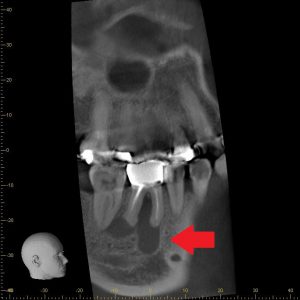

今回のインプラントセミナーでは「抜歯即時埋入・即時荷重」という方法を学びました✏️

一般的にインプラント治療歯の抜けた部分の骨が治癒するのを待って治療を進めていきます。しかし今回のセミナーで学んだのは”抜歯してすぐにインプラントを埋めて、条件が整えば仮歯を入れて機能させる“という方法です✨